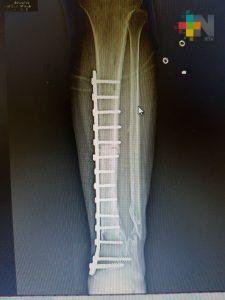

Xalapa, Ver.- Un equipo médico multidisciplinario del Instituto Mexicano del Seguro Social (IMSS) en Veracruz restituyó 11 centímetros de hueso de la pierna de un hombre que sufrió un accidente, mediante el trasplante de tejido óseo cadavérico que le permitió conservar la extremidad y volver a caminar.

El hueso implantado se obtuvo del Banco de Tejidos en el Estado de México a solicitud expresa de los médicos tratantes. El injerto fue realizado en el Hospital General de Zona No. 11 «Ignacio García Téllez», de la ciudad de Xalapa.

Fue aproximadamente una pérdida de 11 centímetros de hueso, por lo que al llegar al hospital se le realizaron cirugías para preservar la viabilidad de los tejidos afectados y la colocación de placas en las partes óseas.

Sin embargo, se buscó la forma de salvar el miembro y mediante la recuperación de la viabilidad de los tejidos blandos se optó por el implante óseo. El doctor Morales explicó que en este caso se activó el protocolo para solicitar tejido óseo y al cabo de algunos meses se logró obtener el hueso de un cadáver apto para implantarse.

Fue necesario recurrir a un implante de hueso porque era una lesión muy extensa. No había sustento, no había hueso, no había de dónde fijar la placa. Era prácticamente una pérdida total, el pie estaba suelto y no había soporte que uniera esas dos estructuras, explicó el especialista. El riesgo de pérdida de la extremidad fue alto y el proceso de recuperación fue de aproximadamente un año.

La recuperación del hueso está al 100, ya tiene una integración radiográfica del injerto y debe continuar con el ejercicio de deambulación, puntualizó.